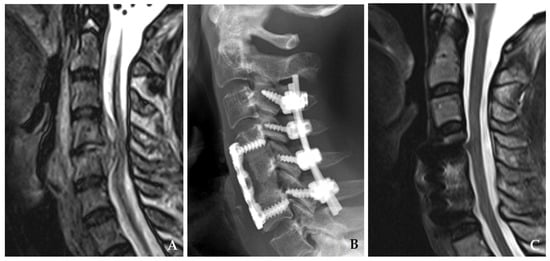

Cervical pyogenic spondylitis (CPS) is an uncommon but clinically significant subtype of vertebral osteomyelitis, accounting for 3–6% of all pyogenic spinal infections [1,2,3]. Despite its rarity, CPS poses a substantial threat due to the cervical spine’s close relationship with the spinal cord and brainstem. Even minor infections in this region may lead to rapid neurological deterioration or death, highlighting the importance of prompt diagnosis and management [4] (Figure 1).

Figure 1. Plain radiograph (A) and magnetic resonance imaging (B,C) demonstrate destructive changes in the C3–C4 vertebral bodies with kyphotic deformity accompanied by retropharyngeal and epidural abscesses compressing the spinal cord.